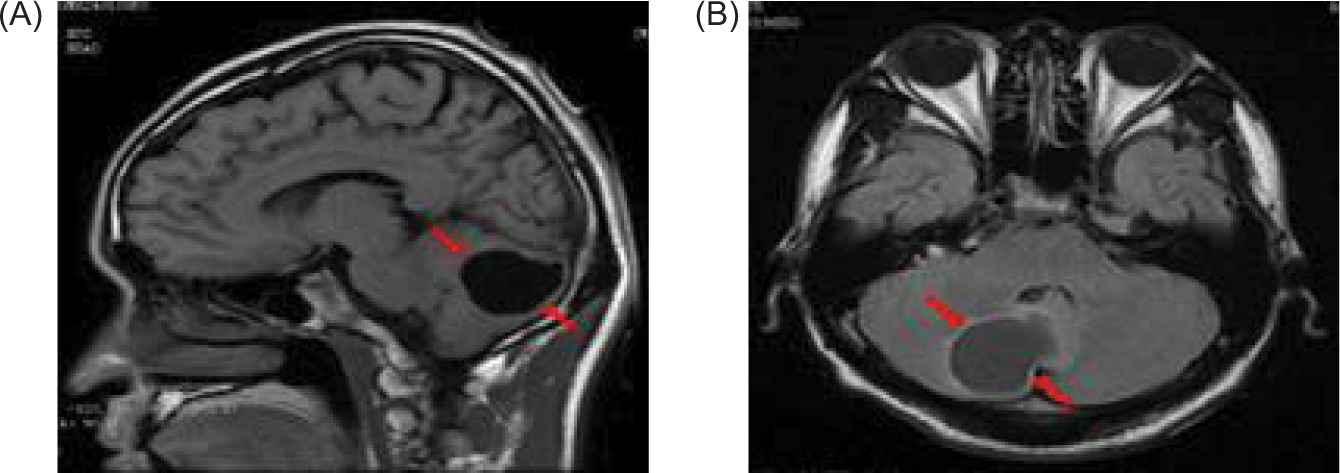

Brain MRI revealed a cystic mass in the right cerebellar hemisphere measuring approximately 40 mm (Figure 6). Thyroid color Doppler ultrasound revealed solid and cystic nodules in both thyroid lobes (C-TIRADS: Category 3) (Figure 7). His fasting blood glucose level was 20.6 mmol/L. On November 29, 2024, he was treated with intensive insulin therapy, and his antidiabetic regimen was adjusted to injection aspart insulin, 4 units tds daily before meals and injection degludec insulin, 5 units once daily at night. The patient’s fasting blood glucose stabilized at 4.5–5.0 mmol/L, and postprandial blood glucose stabilized at 6.0–8.0 mmol/L in 3 days before discharge, and his clinical manifestations, such as polydipsia and weakness in the lower limbs, decreased significantly.

Figure 6: Magnetic resonance imaging (MRI) of the brain reveals a cystic mass in the right cerebellar hemisphere, approximately 40 mm in size (red arrow); (A) sagittal position, and (B) flair view.